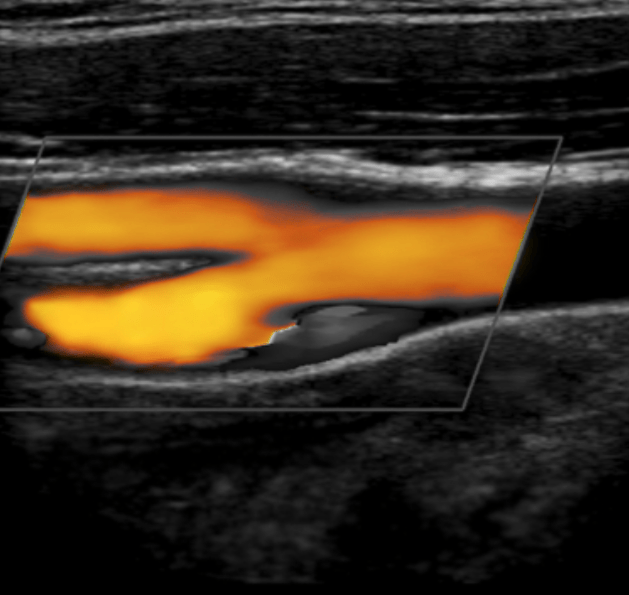

Anche affrontare un pomeriggio ambulatoriale a dopplerare in lungo e largo (o meglio in assiale e trasversale) le carotidi.

Inoltre la seduta di oggi è particolarmente fastidiosa.